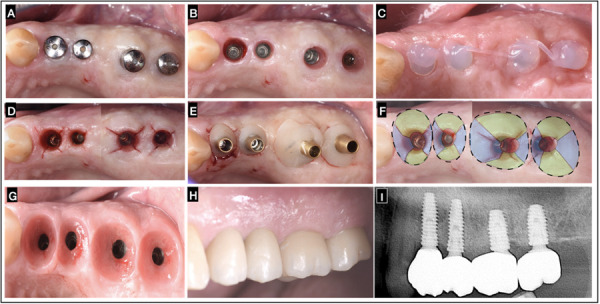

In dentistry, predictable and successful implant treatments demand a comprehensive understanding of the biological mechanisms related to hard and soft tissue changes. The objective of this case reports is to describe in two patients, the conditioning of the implant supracrestal complex (ISC) through the "X Technique", aiming to achieve an enhanced muco-cervical imprint of an individualized emergence profile conformer, reproducible for the emergence profile of the final prosthetic restoration, safeguarding ISC health with the use of active oxygen/lactoferrin gel (blue®m) and ISC stability with the proposed surgical-prosthetic protocol. The technique involves oblique subperiosteal incisions in an "X" pattern with meticulous tissue manipulation to modify peri-implant mucosa phenotype, enhance the buccal contour, and stimulate papilla formation without resorting to additional mucosal grafts. Clinical significance: The technique described offers a promising approach in obtaining a predictable and reproducible muco-cervical imprint or footprint of the prosthetic emergence profile framed within the ISC. Offering to achieve key parameters such as supracrestal tissue height (STH), ISC integrity, muco-cervical imprint stability and implant mucosa thickness (MT) displaying stability. This underscores the effectiveness of the technique in ensuring the sustained health and aesthetics of peri-implant tissues. Further long-term studies are needed to quantify the benefits of this technique in increasing keratinized tissue width (KTW) and MT effectively.